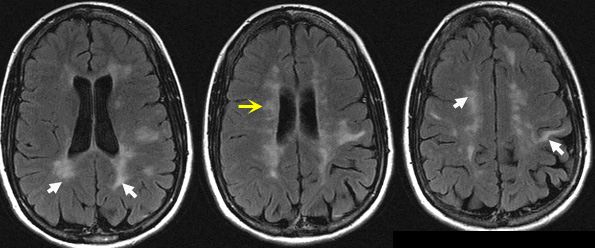

FLAIR images show asymmetrical, abnormal high signal white matter lesions in the periventricular and subcortical areas (white arrows).

Yellow arrow is pointing to lesions around the ventricles (Dawson's fingers).